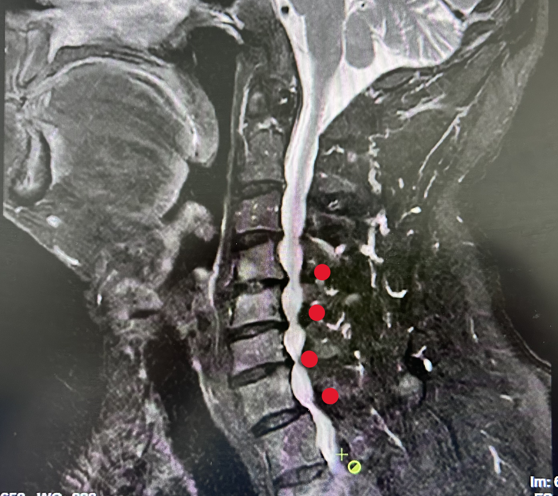

三个月前,高先生被确诊为脊髓性颈椎病。作为颈椎病中最凶险的类型,脊髓型颈椎病因颈椎间盘退变、骨赘增生等压迫脊髓,可引发下肢踩棉感、大小便功能障碍,若延误治疗,脊髓长期缺血缺氧将导致不可逆性瘫痪。高先生颈椎CT及MRI 显示多个节段椎管严重狭窄,脊髓受压程度严峻,手术干预刻不容缓。

患者影像图片(红点部分是被压迫的椎管)